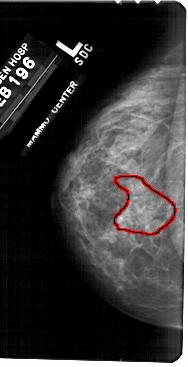

A_1724_1.RIGHT_CC

RIGHT_CC LINES 4906 PIXELS_PER_LINE 2281 BITS_PER_PIXEL 12 RESOLUTION 43.5 NON_OVERLAY

FILE: A_1724_1.LEFT_CC.OVERLAY

TOTAL_ABNORMALITIES 1

ABNORMALITY 1

LESION_TYPE CALCIFICATION TYPE PLEOMORPHIC-FINE_LINEAR_BRANCHING DISTRIBUTION SEGMENTAL

ASSESSMENT 4

SUBTLETY 3

PATHOLOGY MALIGNANT

TOTAL_OUTLINES 1

BOUNDARY